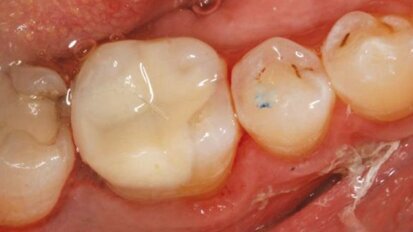

Sealants dentaires: plus seulement pour les enfants

Les sealants dentaires, ces matériaux plastiques, appliqués directement sur les faces occlusales des dents pour prendre place dans les puits ...